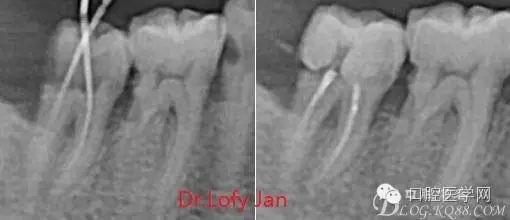

前言:自己做的一些曲面斷層片在未試尖根管治療中的病例整理,發(fā)現(xiàn)問題很多包括自身的,技術(shù)的,還有設(shè)備的問題,予以總結(jié)整理并期待進(jìn)一步提高。

根管治療術(shù)是牙體牙髓疾病治療中最復(fù)雜和最關(guān)鍵的治療項(xiàng)目。根管充填材料抵達(dá)根尖、并能嚴(yán)密堵塞根尖孔,是確保根管治療效果的關(guān)鍵指標(biāo)。為了保證根管充填到位,醫(yī)生需要在術(shù)前照牙片以了解牙根根管的數(shù)量、彎曲程度和長度,在術(shù)中有時(shí)需要插針照牙片來精確測量根管長度,術(shù)后必須照牙片以確定是否根管充填到位,如果欠填或超填,就需要重新充填、重新照牙片確認(rèn),直到根管充填到位。所以,在患者接受根管治療時(shí)有時(shí)會反復(fù)照牙片。

《數(shù)字化根尖片、曲面斷層片、CBCT測量牙齒長度準(zhǔn)確性的比較研究》文中顯示:平行投照數(shù)字化根尖片影像長度和牙齒實(shí)際長度之間無顯著性差異(P0.05);數(shù)字化曲面斷層片影像長度和牙齒實(shí)際長度之間有顯著性差異(P0.05),平均失真率為17.05%。CBCT冠狀面測量結(jié)果中除上頜前磨牙區(qū)、下頜前磨牙區(qū)與真實(shí)長度差異無統(tǒng)計(jì)學(xué)意義(P0.05)外,其余6個(gè)分區(qū)差異均有統(tǒng)計(jì)學(xué)意義(P0.05);矢狀面測量結(jié)果中上頜磨牙區(qū)、下頜磨牙區(qū)、下頜前磨牙區(qū)、下頜尖牙區(qū)、下頜前牙區(qū)與真實(shí)長度比較差異均有統(tǒng)計(jì)學(xué)意義(P0.05)。結(jié)論平行投照數(shù)字化根尖片較曲面斷層片和CBCT能更加精確地反映牙齒的真實(shí)長度。

病例分析:曲面斷層片在x線輔助診斷與檢查中目前大多數(shù)文獻(xiàn)和著作都建議只能作為初診拍片檢查手段,不能作為終末疾病的確診與手術(shù)療效的評價(jià)指標(biāo),臨床大部分中小型門診都因?yàn)樵O(shè)備不齊全導(dǎo)致信息偏差很大。